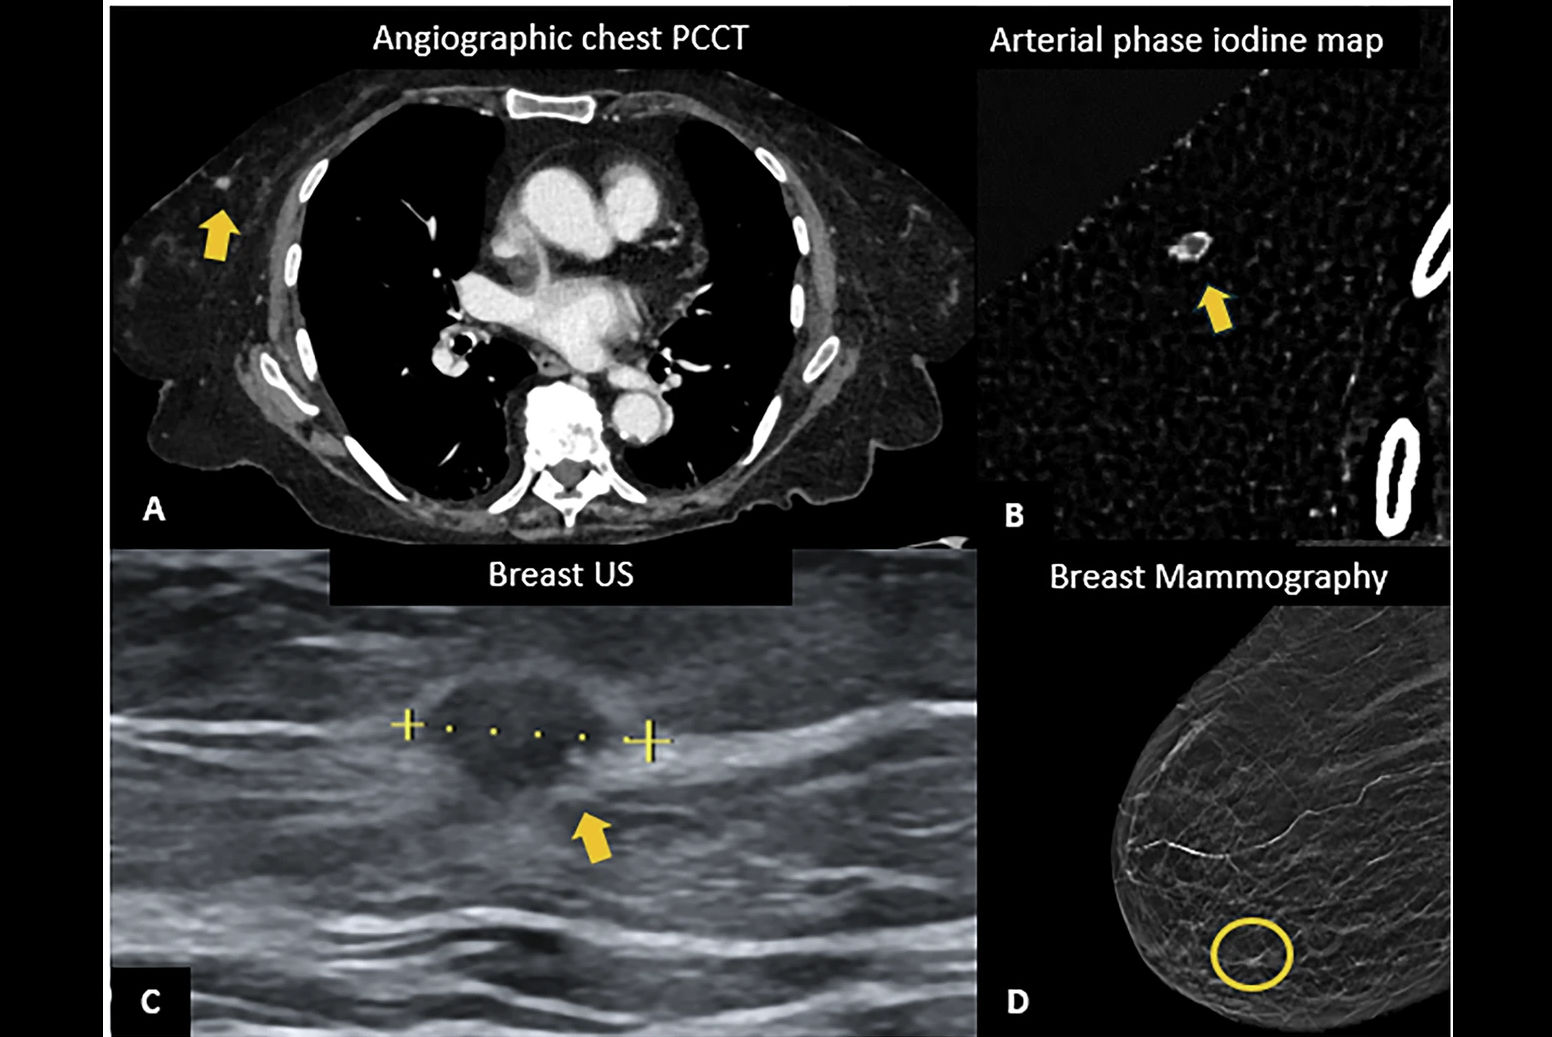

CT Eye helps radiologists identify signs on chest CT imaging associated with pulmonary embolism, lung nodules, and lung consolidation and prioritizes studies with these types of findings.